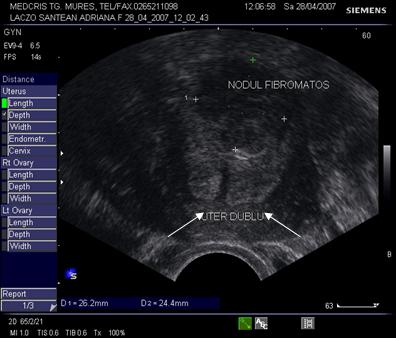

Fig. nr. 98. Uter dublu cu nodul fibromatos intre cele doua corpuri. Se remarca (cu sageti) cele doua ecouri endometriale, la ecografia vaginala

Fig. nr. 99. Ecografia abdominala 3 D de suprafata, indica prezenta unui nodul fibromatos (cu doua sageti) intre cele doua corpuri uterine (cu cate o sageata) la aceeasi pacienta ca in figura precedenta